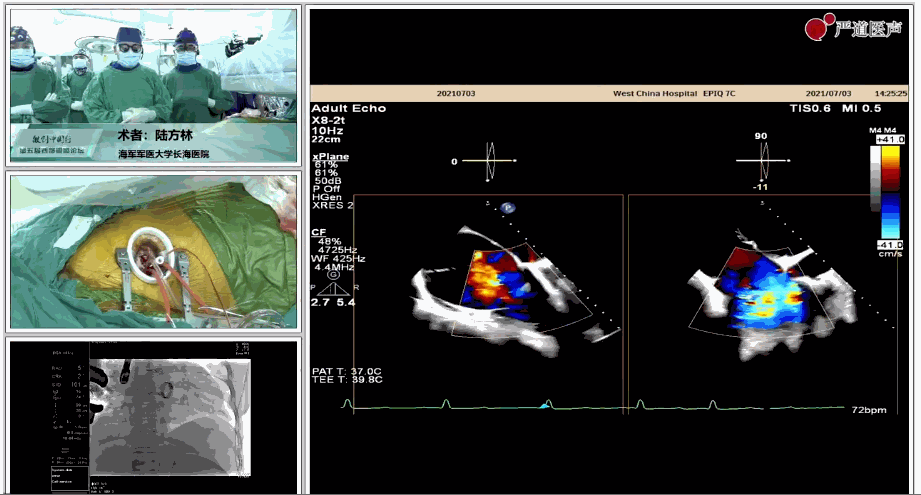

7月3日下午,海軍軍醫(yī)大學(xué)附屬上海長海醫(yī)院心血管外科徐志云、陸方林團隊在論壇中分享了經(jīng)導(dǎo)管三尖瓣置換術(shù)(LuX-Valve®)的手術(shù)直播演示。線下會議由陶涼教授、潘文志教授、喬晨暉教授共同參與討論和臨床分享。

陸方林教授分享的是一例極重度三尖瓣返流的患者采用健世科技(LuX-Valve®)經(jīng)導(dǎo)管三尖瓣置換系統(tǒng)進行的手術(shù)直播演示。此例患者為69歲女性,入院前17年行二尖瓣機械瓣置換術(shù),術(shù)后長期服用華法林抗凝,既往“2型糖尿病”病史5年,“雙下肢水腫”3年。3個月前患者出現(xiàn)腹脹、雙下肢水腫,伴活動后暈厥,伴黃疽、皮膚濕癢、牙齦出血,癥狀持續(xù)加重,遂入院治療。入院后行心臟CT、心臟超聲檢查,提示:“三尖瓣關(guān)閉不全(極重度),二尖瓣置換術(shù)后,心功能III級”。徐志云、陸方林微創(chuàng)三尖瓣置換團隊對該患者的病情進行了充分的評估和討論。由于患者有開胸二尖瓣置換手術(shù)史,且病史時間長,同時存在相關(guān)合并癥,傳統(tǒng)外科手術(shù)風(fēng)險極高(STS評分:8.315%),最終決定采用三尖瓣LuX-Valve®瓣膜系統(tǒng)對患者進行治療。

▲術(shù)中食道超聲顯示三尖瓣極重度返流